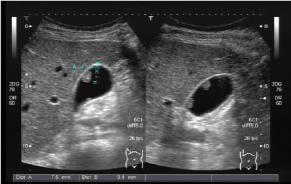

超音波検査

超音波検査とは

超音波検査は、エコー検査とも呼ばれています。お腹の赤ちゃんを見るときと同じ検査です。体の中での音波の反射を利用して臓器の形態や血流などを観察する検査です。耳では聞くことができない高い周波数の音波(超音波)を使用しています。

超音波検査でこんなことが分かります

| 腹部超音波 | 脂肪肝、胆嚢ポリープ、胆嚢結石、腎結石、良性(悪性)腫瘍など |

| 甲状腺超音波 | 甲状腺腫瘍、頸部のリンパ節 |

経腟超音波検査のおすすめ

通常の子宮頸がん検診は、細胞を取り調べる検査であり、子宮や卵巣の状態を画像でとらえていません。右記のようなお悩みがあり画像診断をご希望される方は、経腟超音波検査をおすすめします。

内診に続いて検査を行います。通常痛みはなく、1~2分程度で終わります。